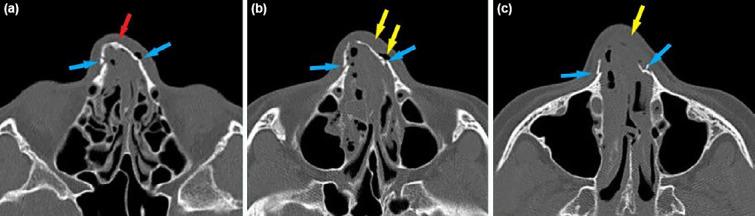

In the study, 1225 patients were evaluated, and 98.7% of them were women (mean age 35 [IQR: 17] years). Of the pa-tients, 63.1% were high school and university graduates. The rate of married women was 74.6%. No relationship was found between gender, age, educational status, and marital status (p>0.05). Most of the traumas were minor (85.4%) and blunt (81.9%) trauma, and the most common types of trauma were kicking (49.9%) and punching (47.3%). It was found that the most frequently affected areas of the patients were the head and neck (76.7%), and the frequency of pelvic trauma was high in male patients (p<0.05). The most com-mon bone fracture was nasal (40.5%) followed by ulna fractures (14.5%). The left-sided diaphyseal fractures were the most common in patients exposed to IPV. In our study, the frequency of mortality was 12.9%, and it was found to be significantly higher in males (p<0.05).

本研究共评估了 1225 名患者,其中 98.7%为女性(平均年龄 35 [IQR:17] 岁)。患者中 63.1%为高中和大学毕业生。已婚女性的比例为 74.6%。性别、年龄、教育程度和婚姻状况之间无相关性(p>0.05)。大多数创伤为轻微(85.4%)和钝性(81.9%)创伤,最常见的创伤类型为踢打(49.9%)和拳打(47.3%)。发现患者最常受影响的部位是头部和颈部(76.7%),男性骨盆创伤发生率较高(p<0.05)。最常见的骨折是鼻骨(40.5%),其次是尺骨骨折(14.5%)。在 IPV 暴露的患者中,左侧骨干骨折最为常见。在本研究中,死亡率为 12.9%,男性死亡率明显较高(p<0.05)。